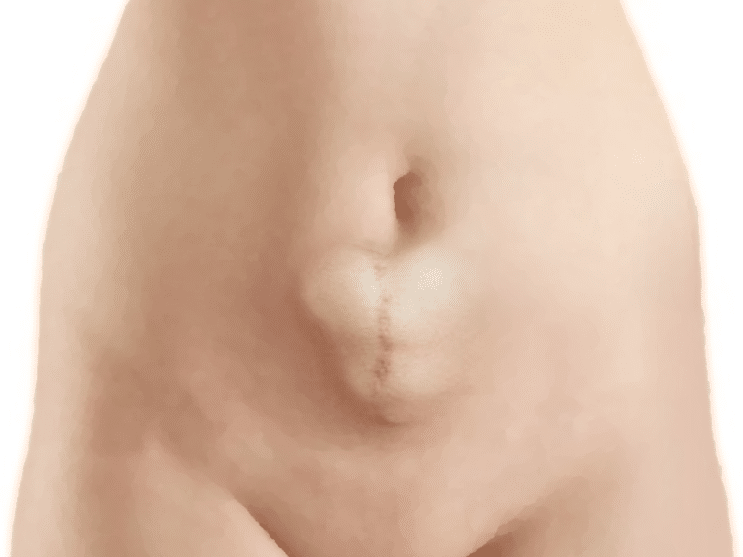

Hernia incisional

Es la protrusión anormal del peritoneo a través de la cicatriz patológica de una herida quirúrgica o traumática.